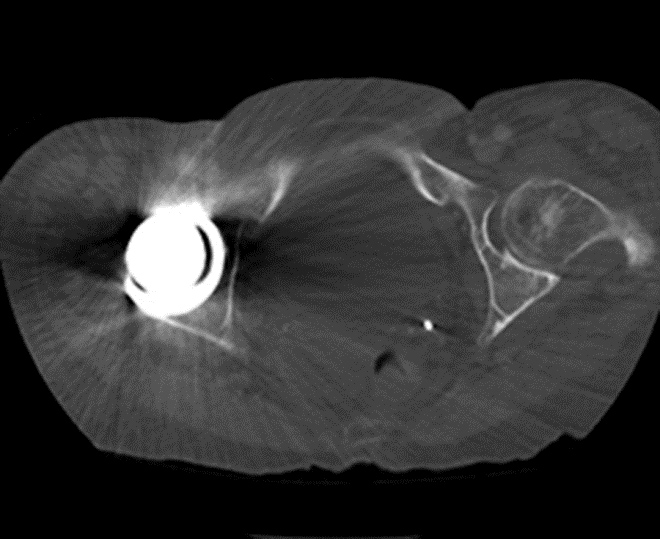

Artifact summation Artifact summation Windowing Windowing

Artifact Summation. (A) Scout image demonstrates bilateral total hip arthroplasties. (B) Axial CT image at the level of acetabular cup and femoral head shows severe transverse streaking related to total summed attenuation of metal components. Optimal Windowing. (A) Axial CT image of the pelvis viewed in soft tissue windows demonstrates extensive streak artifact due to total hip arthroplasty prohibiting evaluation of adjacent bone and soft tissue structure. (B) Same axial CT image set to bone windows results in improved visibility of adjacent bone and soft tissue anatomy.